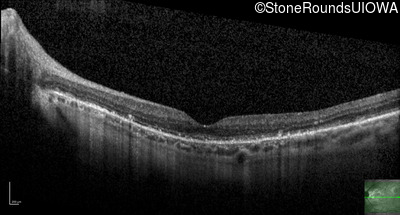

Optical Coherence Tomography - Left - 20/20 -1

Exemplar / OCT Stack

OCT Stack